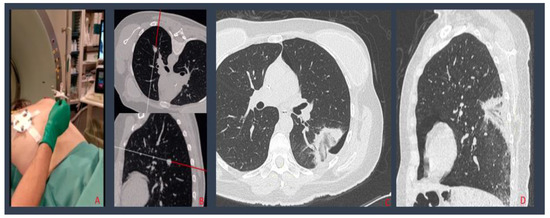

2.2.1. Standard CT-Guided Procedures

2.2.2. SIRIO-Guided Procedures